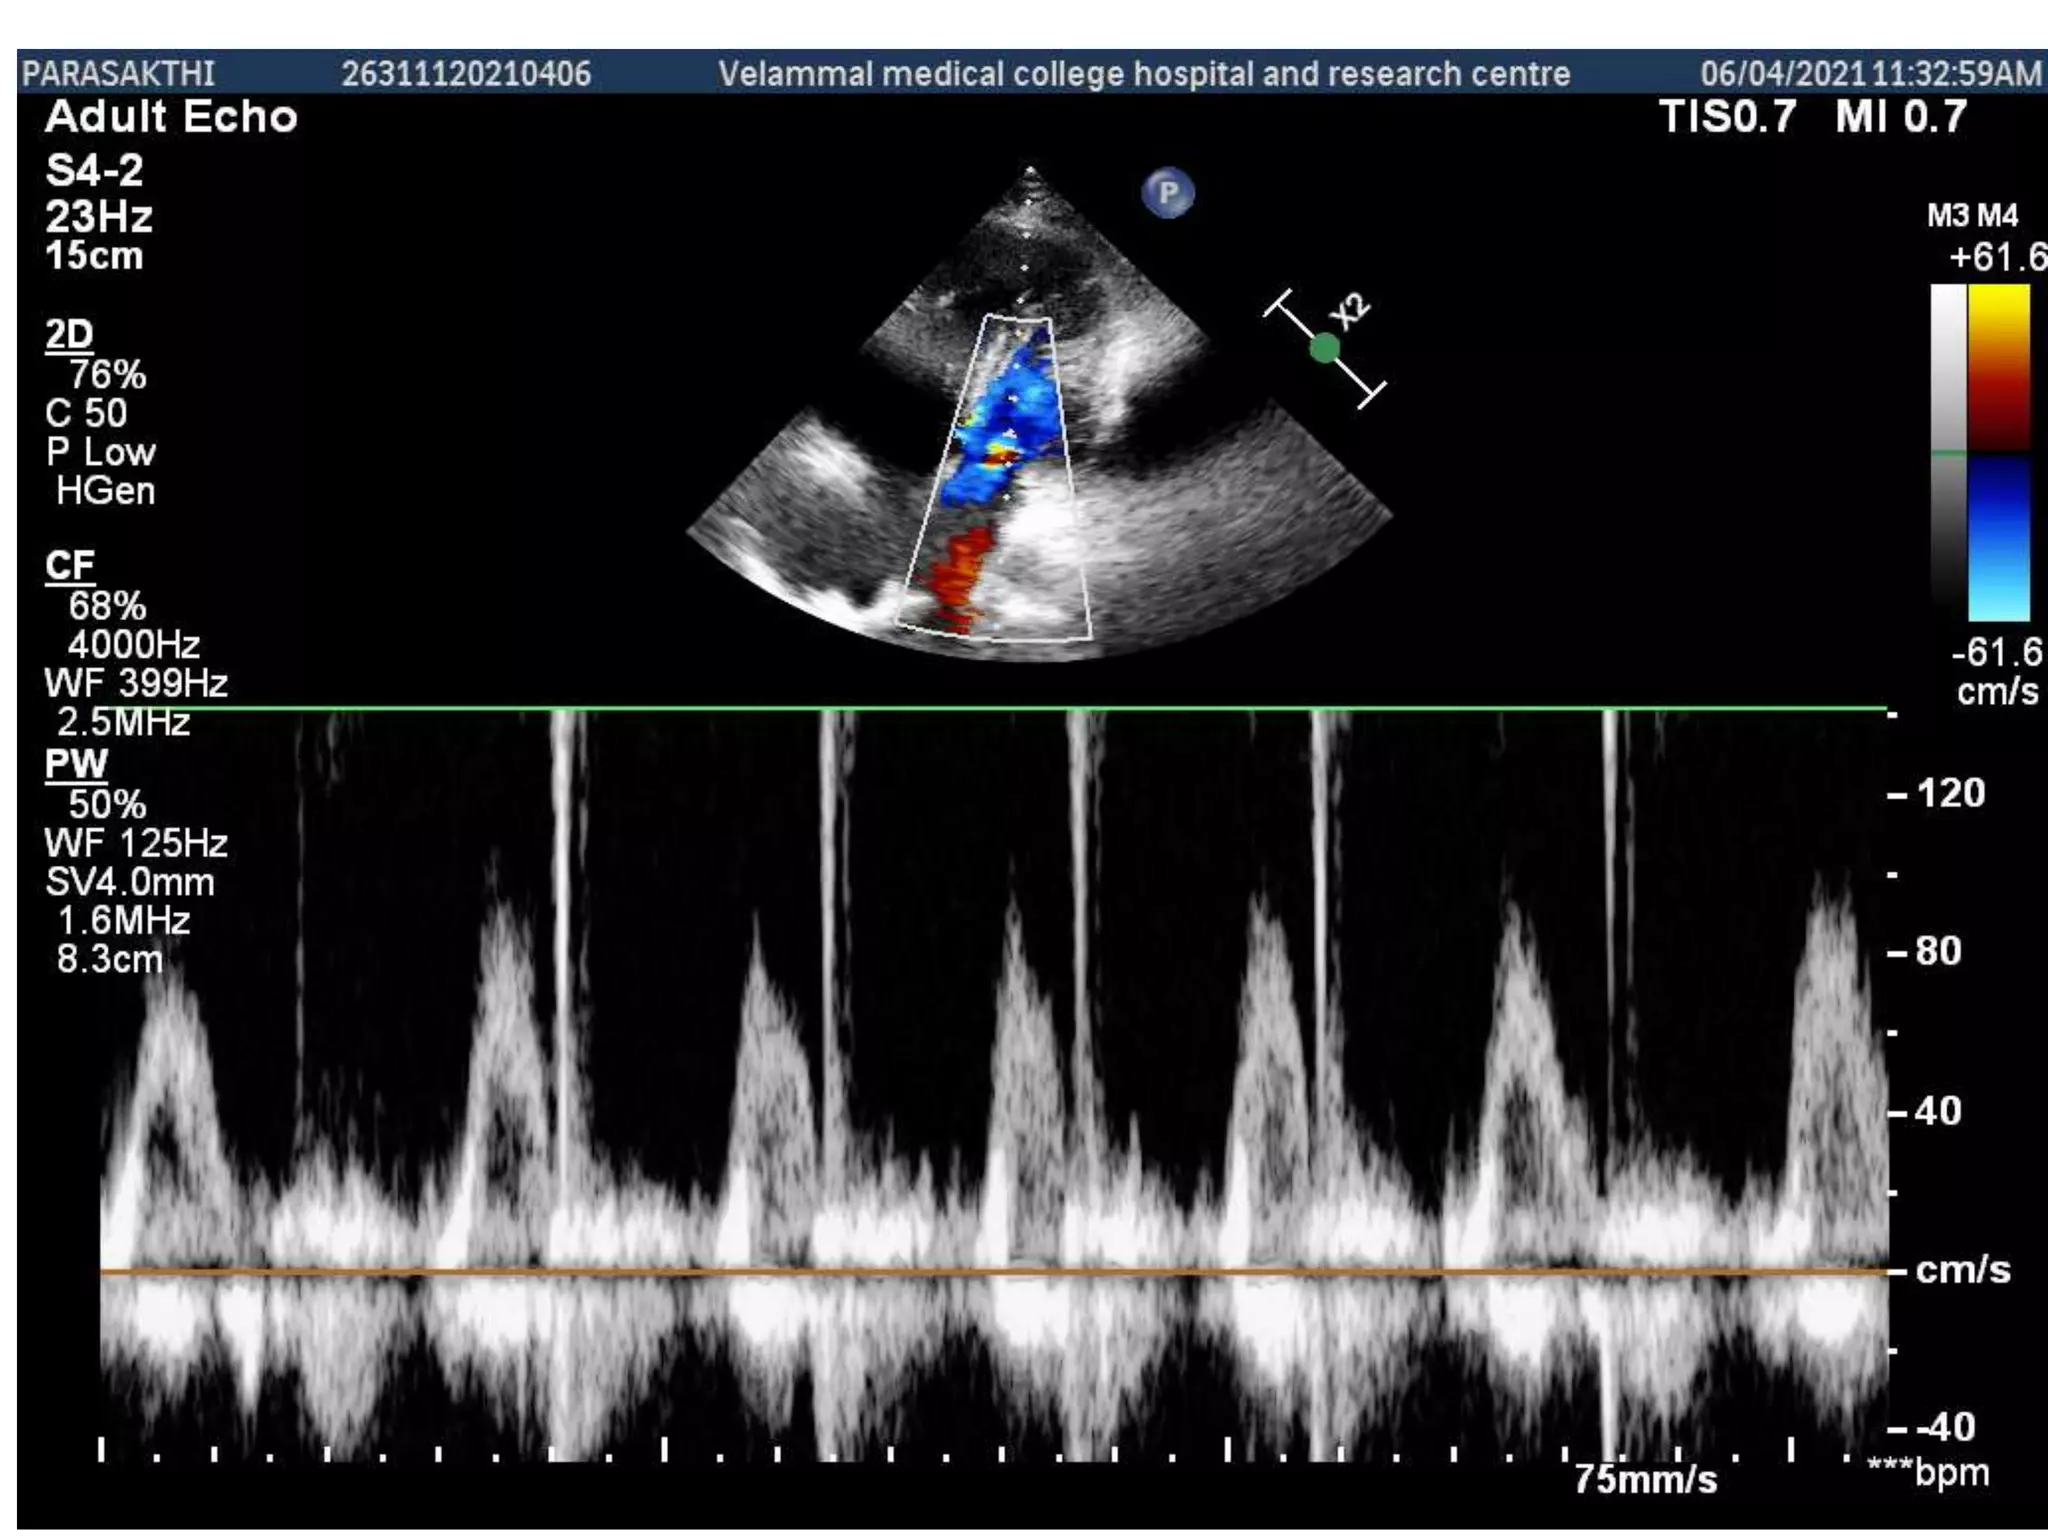

Etimation of systemic flow across the

lvot

Pulmonary flow across the rvot

Etimation of systemicflow across the lvot

• 59.

• 60.

Color flow showinginterartrial septal defect